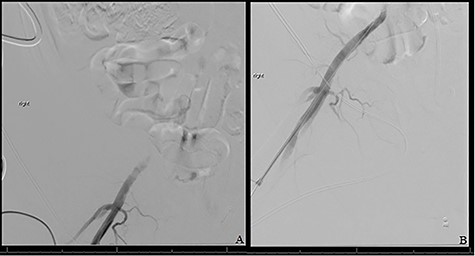

The patient was taken to the operating room immediately for percutaneous balloon angioplasty and stenting of the right EIA. The right femoral artery was accessed, and an angiogram confirmed occlusion of the right EIA. The occlusion was crossed, and an 8-mm Viabahn stent was placed to treat the occlusion. The completion angiogram showed complete revascularization of the right leg (Fig. 3). After hemostasis, the compartmental pressures of the right leg were noted to be normal, and normal Doppler signals were observed.

(A) Shows initial retrograde angiogram of right common femoral artery with occlusion at the level of the EIA. (B) demonstrates restoration of flow postangioplasty and stenting.